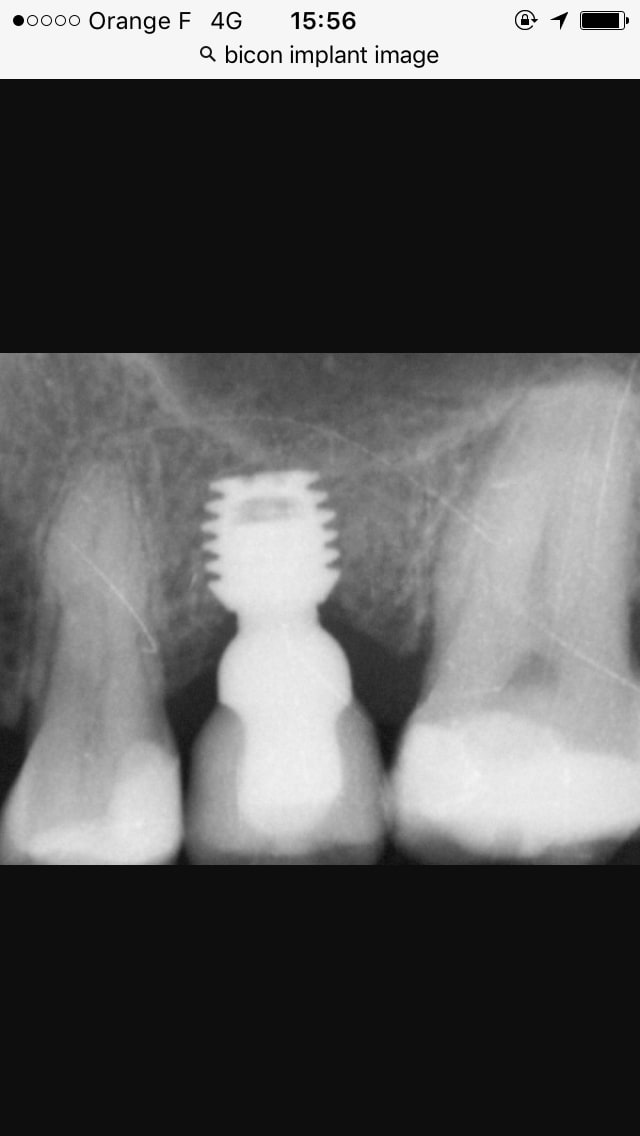

Junior, tu as oublié le Bicon il me semble?

Il est assez original et rencontre son petit succés aux USA

http://www.bicon.com/product_info/pi_new.html

le bicon il n'a pas de vis sur les radios on dirait. C'est un cône morse semble t il.

Bicon n'a pas un profil au niveau des spires qui soit comarables aux implants classiques.

Ses spires sont larges et assez espacees pour constituer des plateaux qui s'opposent aux forces verticales

Bicon n'a pas un profil au niveau des spires qui soit comparable aux implants classiques.

Sur les forums US le bicon a une grosse côte. Je me demande si il n'est pas impacté